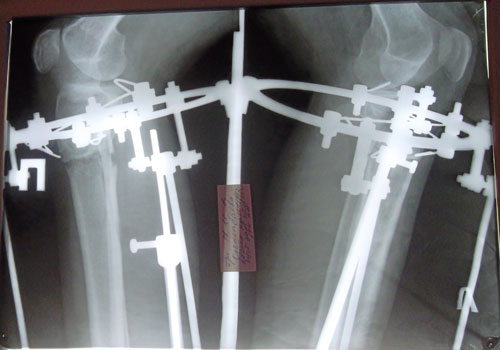

- Диагноз: О-образная деформация ног

- Дата операции.: 25.07.2013